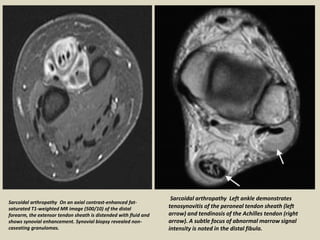

Sarcoidal arthropathy Left ankle demonstrates

tenosynovitis of the peroneal tendon sheath (left

arrow) and tendinosis of the Achilles tendon (right

arrow). A subtle focus of abnormal marrow signal

intensity is noted in the distal fibula.

Sarcoidal arthropathy On an axial contrast-enhanced fat-

saturated T1-weighted MR image (500/10) of the distal

forearm, the extensor tendon sheath is distended with fluid and

shows synovial enhancement. Synovial biopsy revealed non-

caseating granulomas.